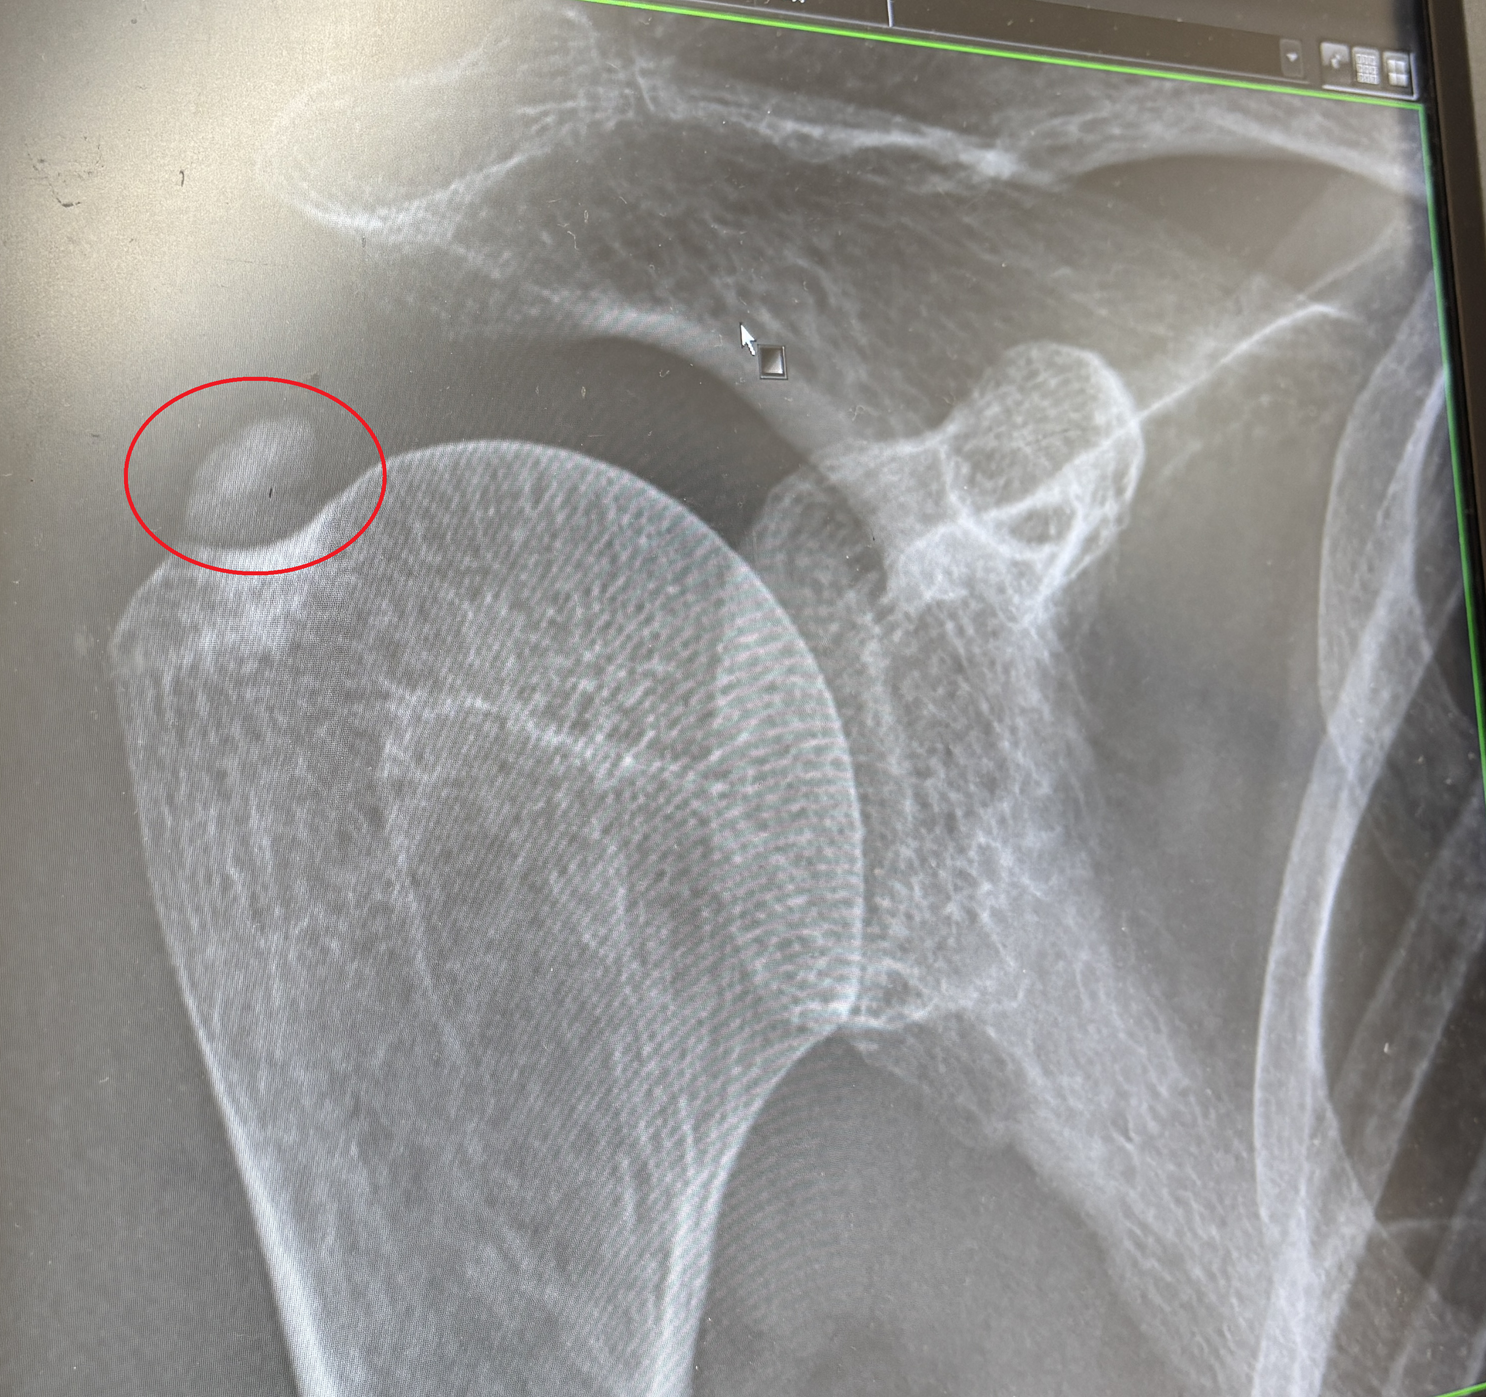

↓「ひざ関節症クリニック」様の画像をお借りしました。

この画像はイメージが分かりやすいです。

最初に痛み止めを打ったときほど、痛みが改善しないので、

画像のようにヒアルロン酸が関節の隙間に入っていないのかな・・・。